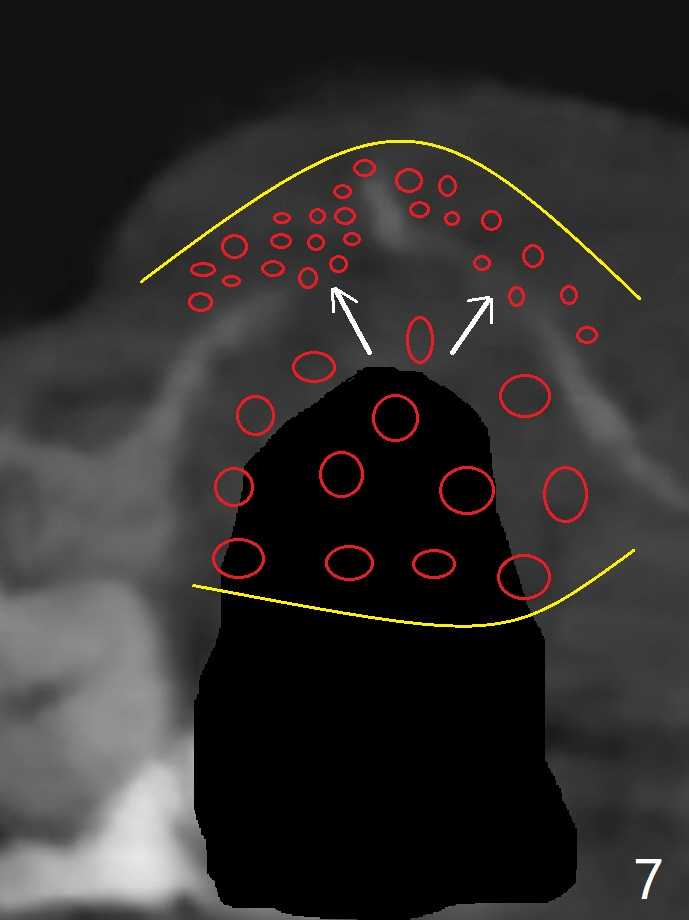

59岁女右上七骨质吸收严重(图一),上颌窦底板薄(图二:*),而窦膜厚(图三:*),应该容易提升,腭侧根吸收(图四:P),上颌窦底板穿孔(图五:*),拔牙后(图六:黑色),水提升(白箭头),放置PRF膜(黄色曲线)和粘性骨块(红色圆圈),最后完成位点保留(图七:大圆圈),放置另外一块PRF膜和6个月吸收膜,缝合,牙周或者树脂敷料。Return to No Deviation 19-21 位点保留后 导板与张口度 Xin Wei, DDS, PhD, MS 1st edition 09/09/2020, last revision 01/01/2021